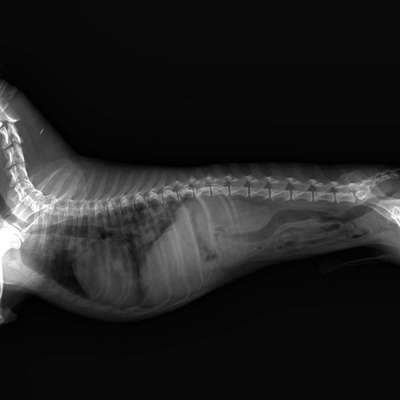

Hallo, mein Hund wurde gestern geröntgt. Mein Tierarzt ist seit der ersten Sekunde der meinungen es handle sich um Tumore in der Lunge. Ich suche daher nach ein paar anderen die sich das Bild mal anschauen und gucken ob es sich wirklich um Metastasen handle oder vielleicht hat jemand mal was anderes gesehen was so aussah. Ich danke schon mal im voraus. Mit freundlichen Grüßen William

Im Bereich der Lunge sind mehrere rundliche, hellgraue „Flecken“ von unterschiedlicher Größe erkennbar, die ein tumoröses Geschehen vermuten lassen.

Das Herz erscheint vergrößert, was hinweisend für ein Herzproblem sein kann. Hierzu müsste allerdings eine spezielle Messung erfolgen!

Im Bauchraum kann ich anhand des Fotos keine Auffälligkeiten erkennen.

Der Magen-Darmtrakt erscheint relativ „leer“ bzw. luftgefüllt.